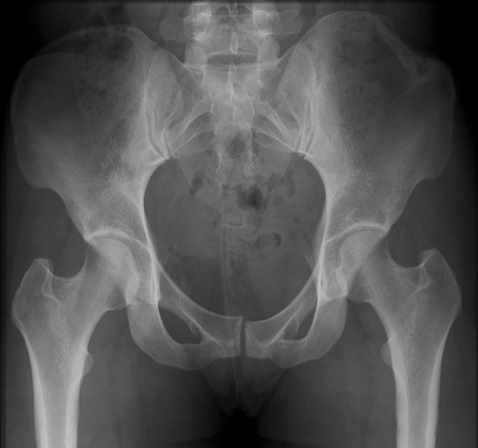

(2)Duverney 骨折

直接暴力导致的髂骨翼单独骨折,没有骨盆环的分离移位。

(3)Pipkin 骨折

髋关节后脱位往往合并股骨头骨折(5-15%)。最早(1957 年)由 Pipkin 描述并分类,因而被命名为 Pipkin 骨折,常见于屈膝屈髋位汽车仪表盘损伤。